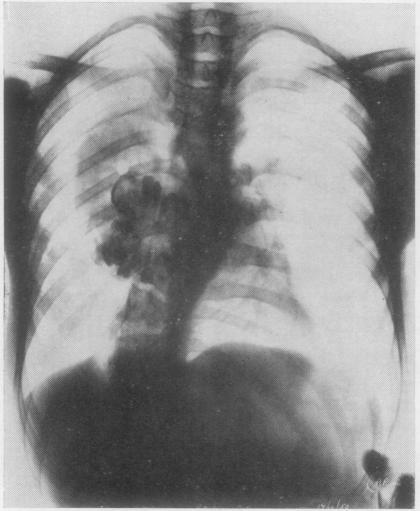

PHILIP W P, HARRISON K, CRUICKSHANK D B

Thorax. 1954 Sep;9(3):245-7. doi: 10.1136/thx.9.3.245.